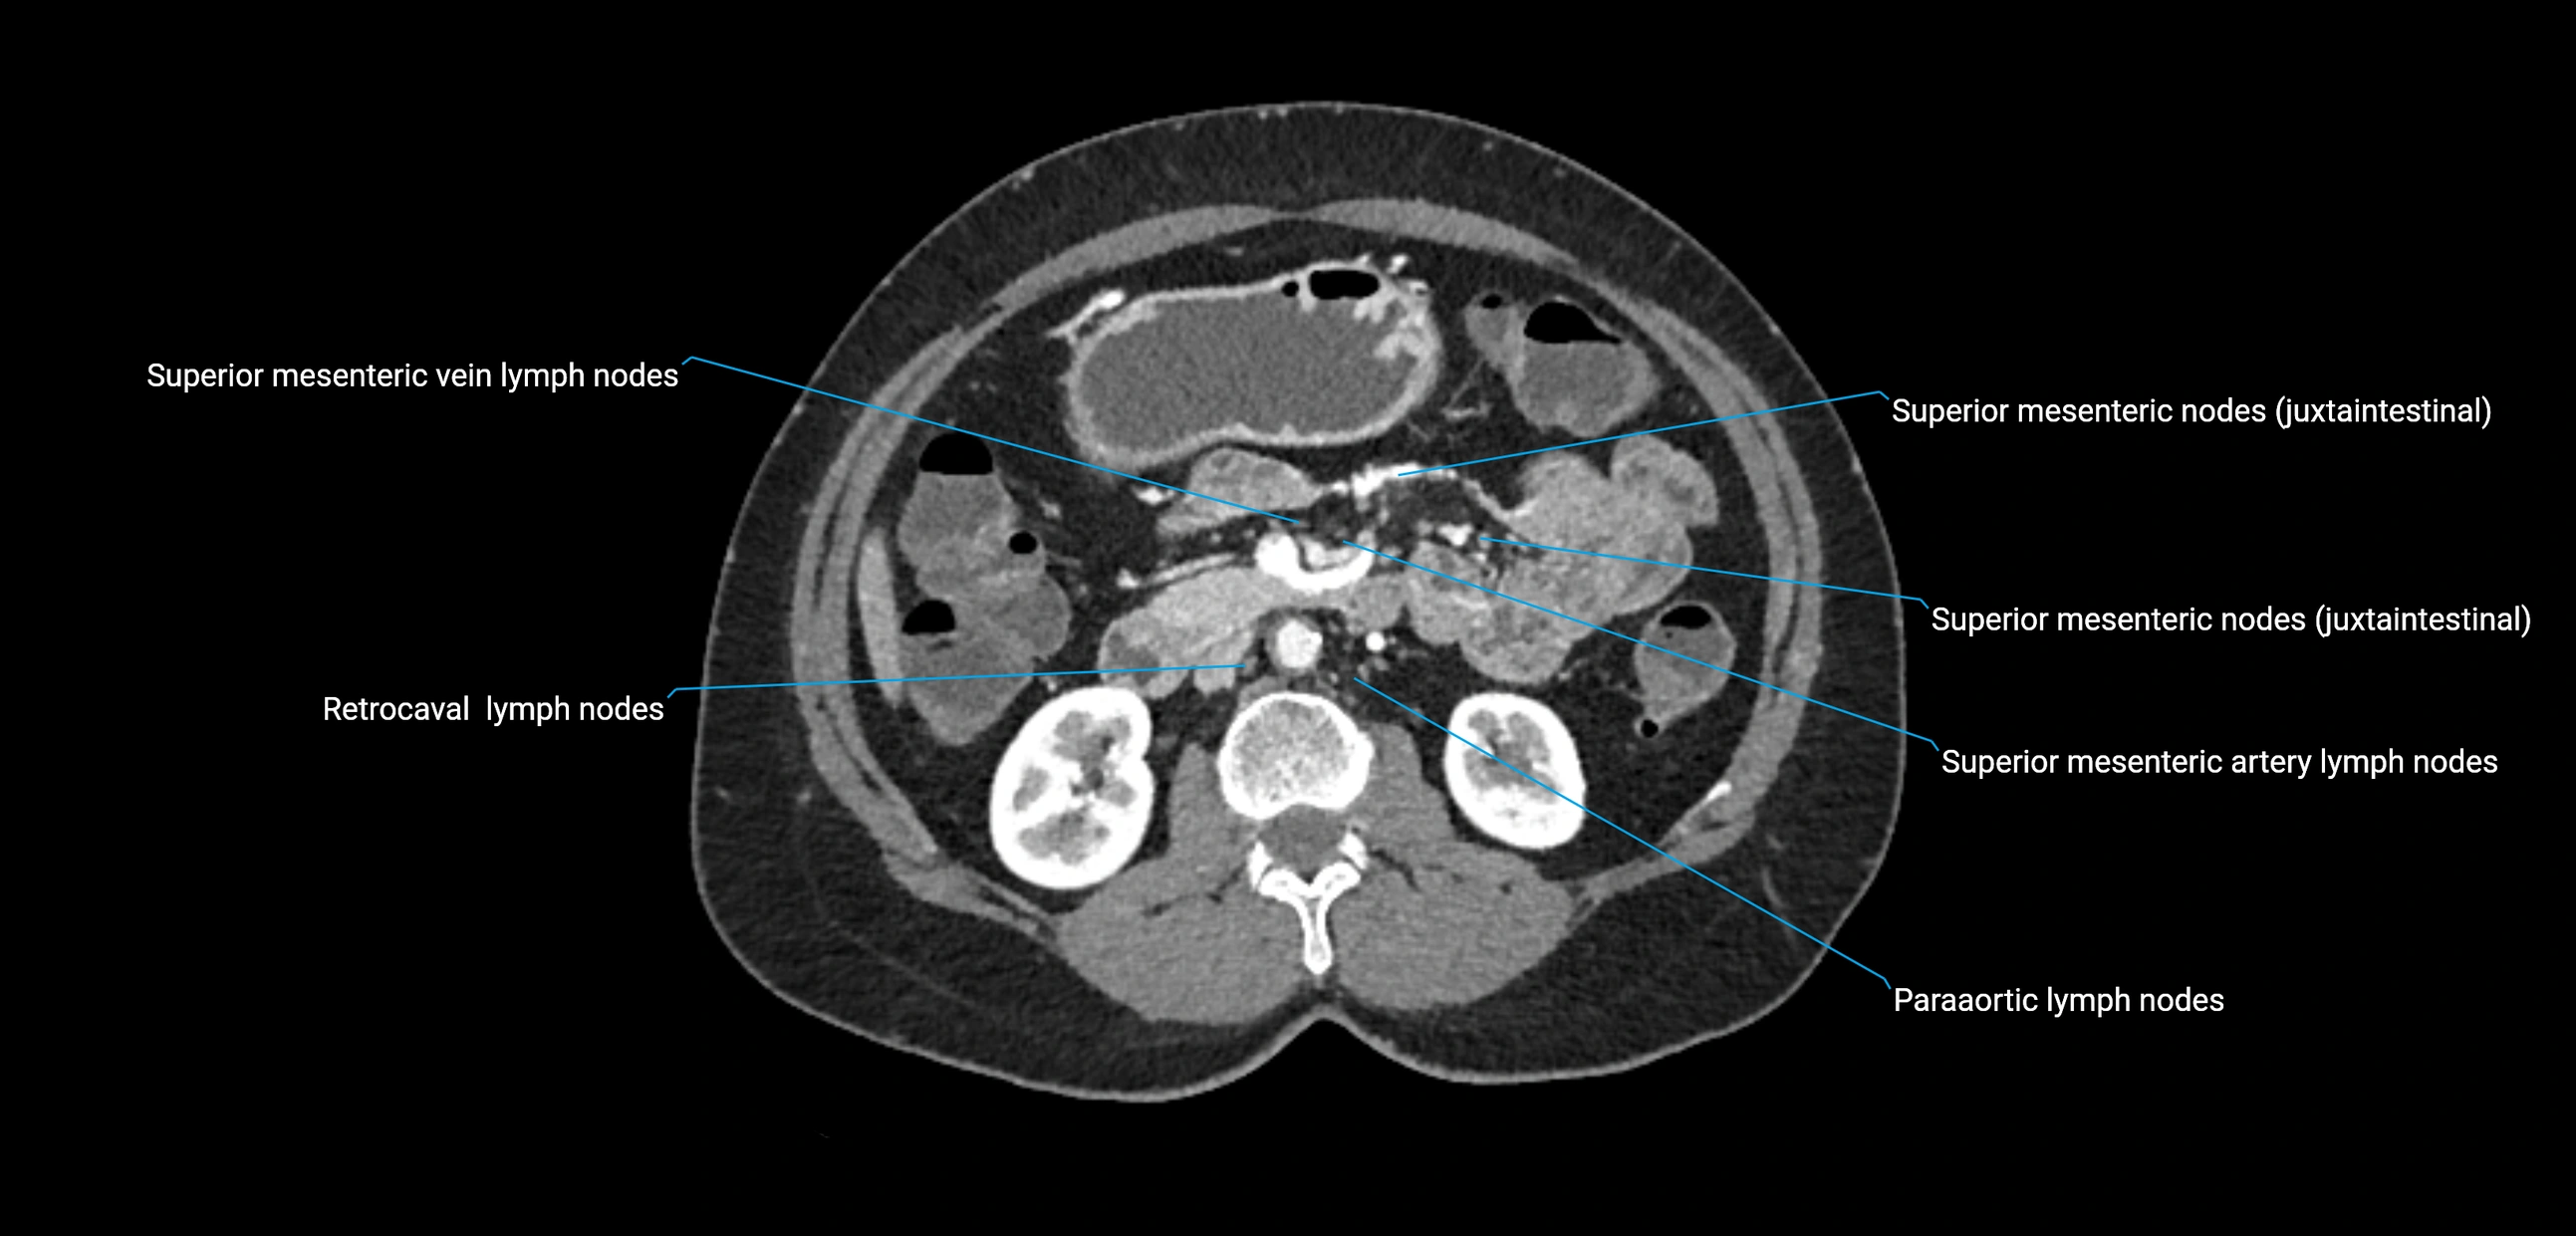

CT Appearance

CT Pre-Contrast:

• Nodes appear as soft-tissue density nodules adjacent to the aorta and IVC

• Calcification may be seen in chronic infections (e.g., tuberculosis)

CT Post-Contrast:

• Normal nodes enhance homogeneously

• Malignant nodes may show heterogeneous enhancement, central necrosis, or conglomerate formation

• Size >1 cm short axis is suspicious, though morphology and distribution are equally important

CT Venography (CTV):

• Demonstrates nodal encasement or compression of adjacent vessels (aorta, IVC, renal veins)

• Useful in staging testicular and ovarian malignancies

• Provides 3D reconstructions for retroperitoneal lymph node dissection planning

CT image

image